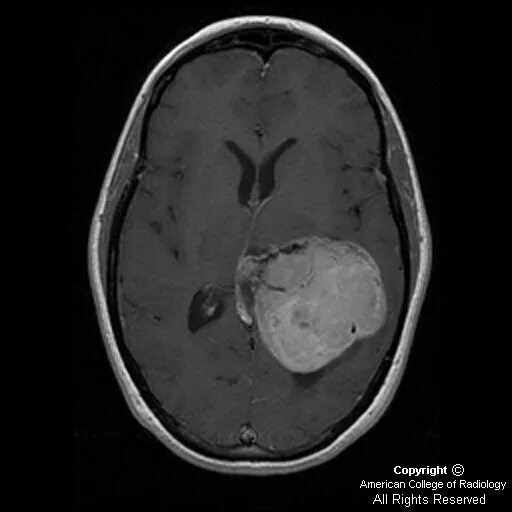

Метастазы в головном мозге мкб